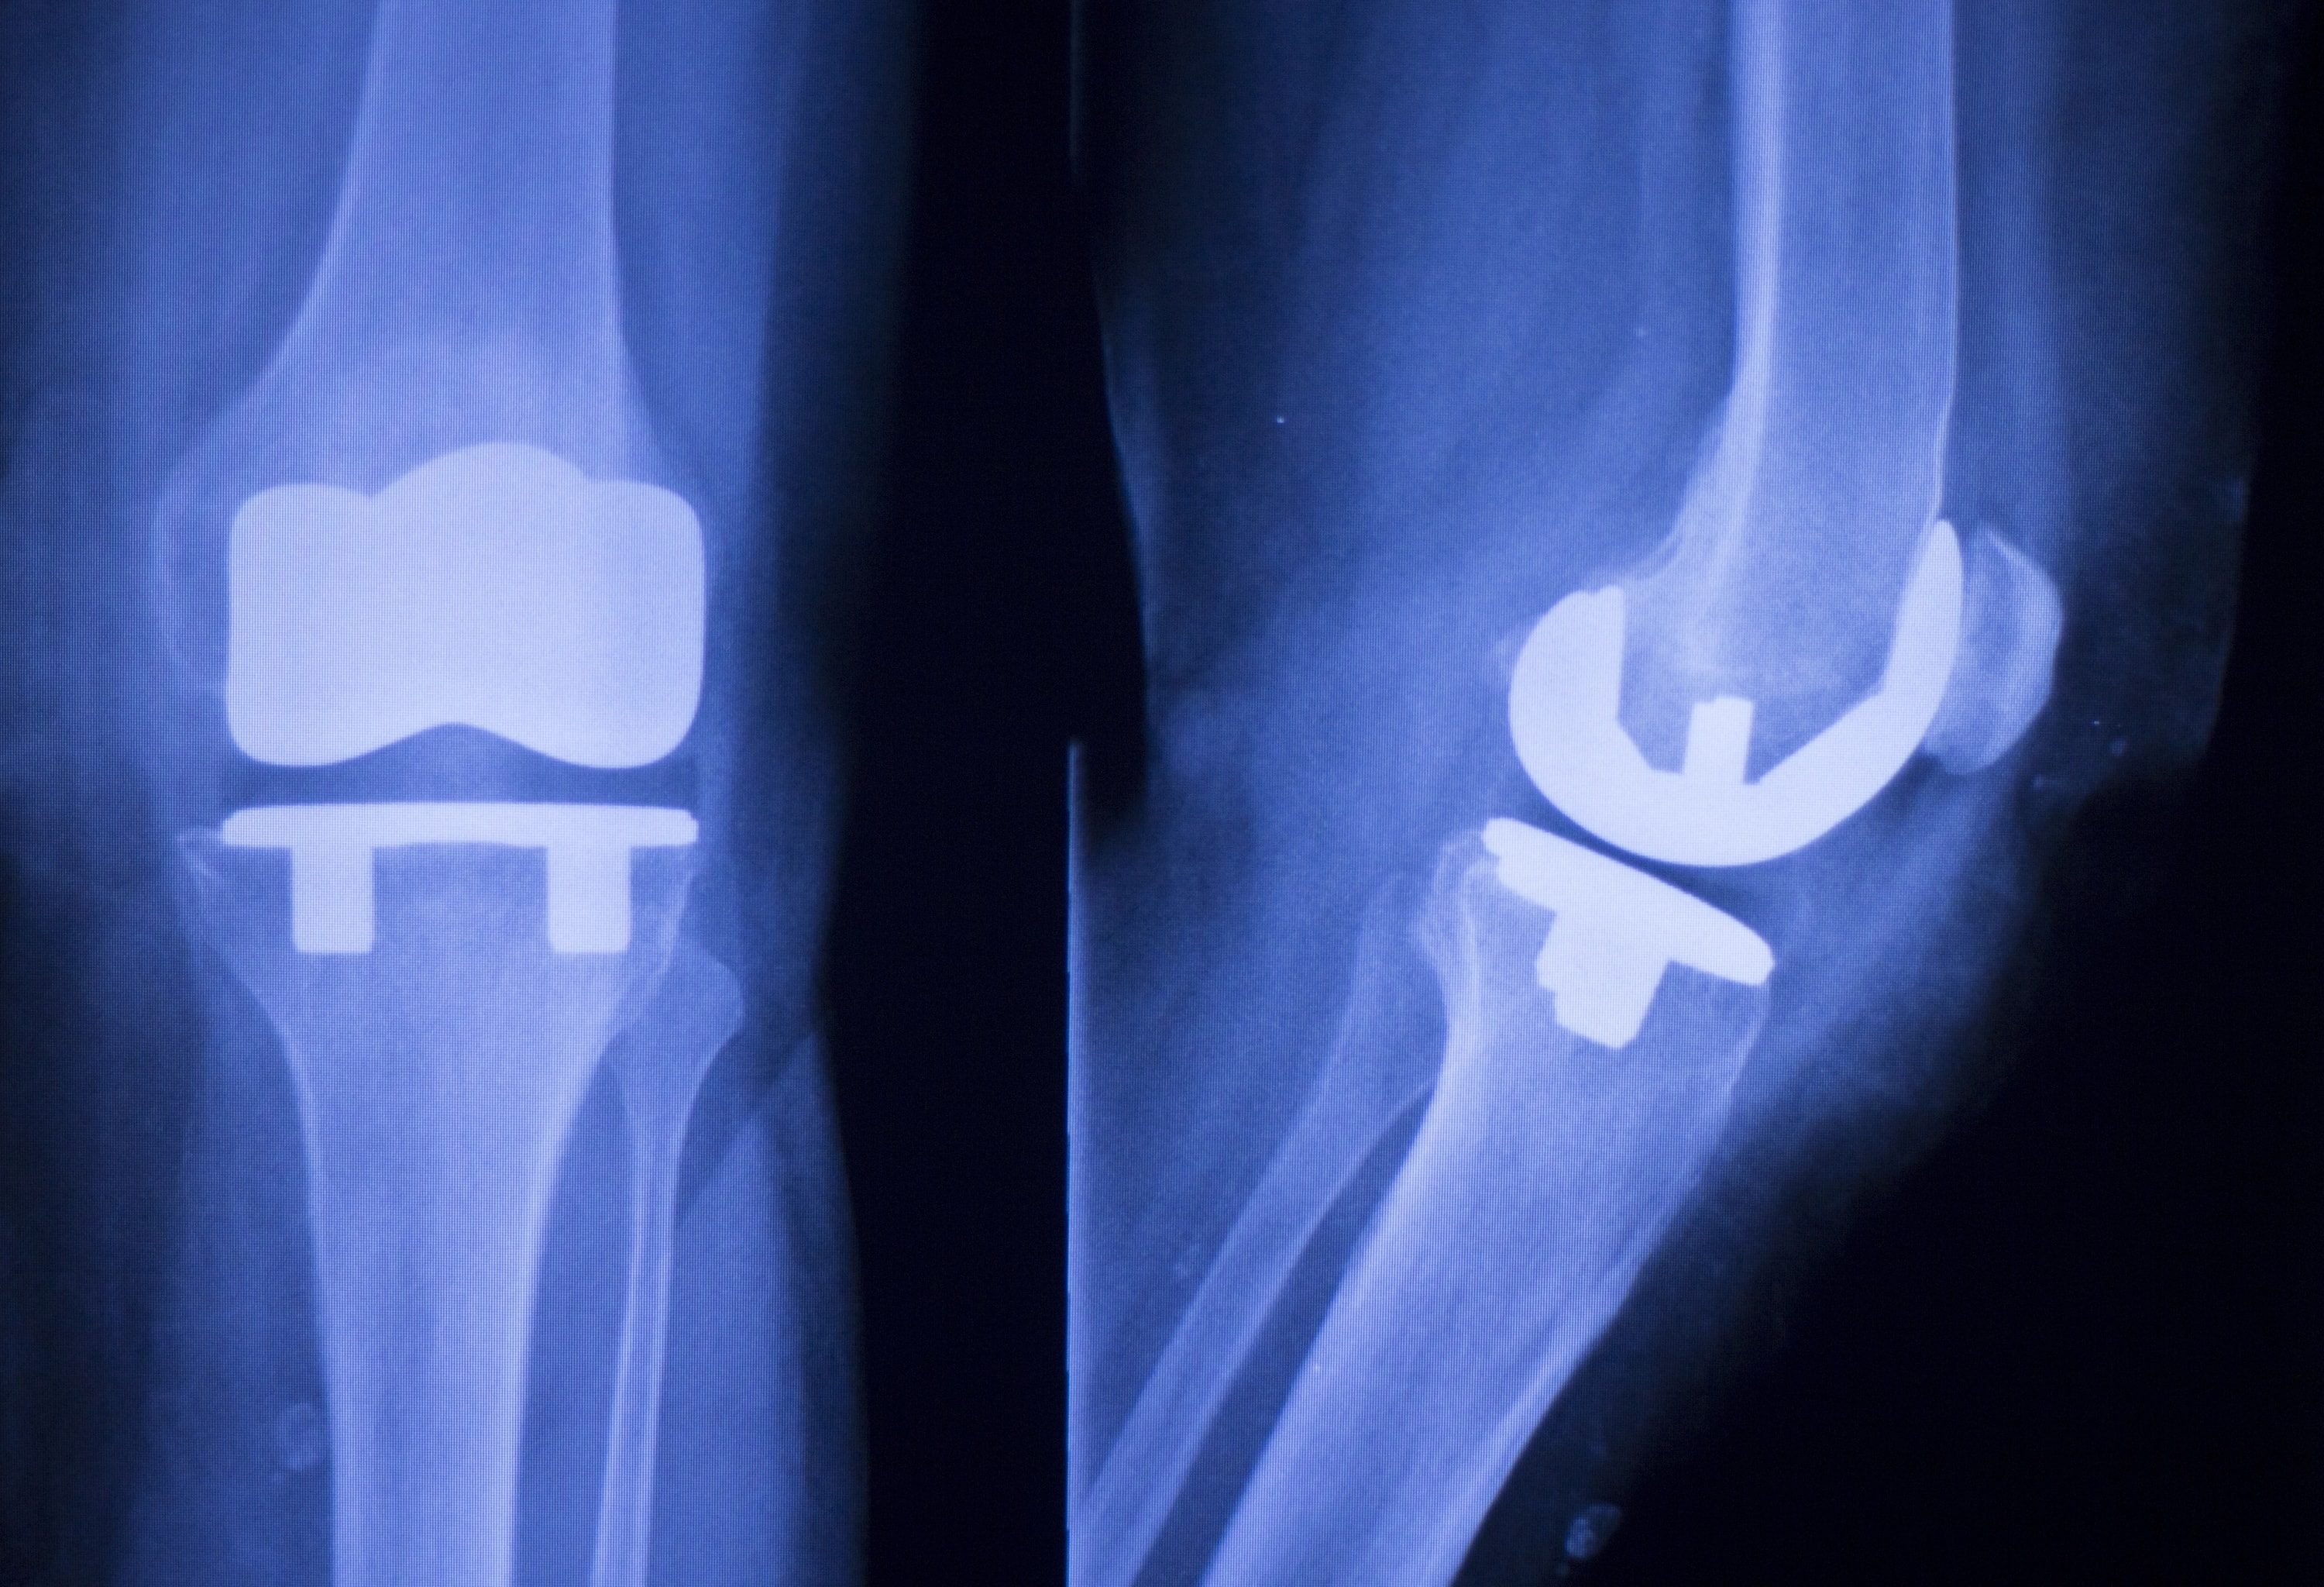

Eine drohende Totalendoprothese-Operation (TEP-OP) für deine Hüfte oder dein Knie lässt sich in vielen Fällen hinausschieben. Im besten Fall gar um Jahre hinauszögern. Falls ein operativer Eingriff wirklich unumgänglich sein sollte, kann die gezielte physiotherapeutische TEP-OP-Vorbereitung von Achilles Altona die Erfolgswahrscheinlichkeit deiner TEP-Operation spürbar erhöhen.